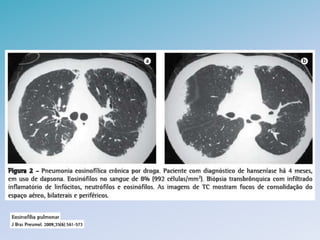

PNEUMONIA EOSINOFILICA AGUDA •Rara, jovens previamente saudaveis • Exposicao ambiental, tabagismo e uso de medicacoes • Febre é sintoma mais comum (< 30 dias) com eosinofilia no LBA (> 25%) descartando outras causas • Histopatologico: infiltracao de eosinofilos e macrofagos no intersticio e espacos alveolares. Podem formar microabscessos

• 16.

• 17.